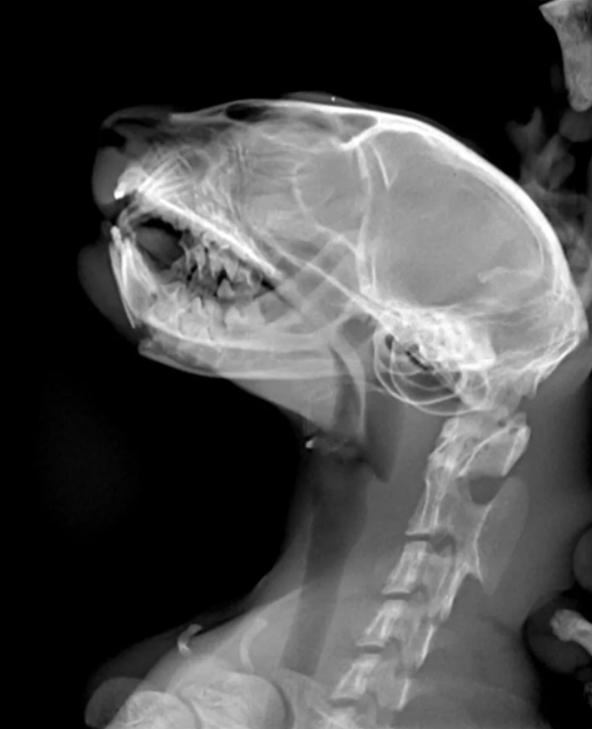

(三)

下颌骨骨折的猫咪很可能出现

明显异常的面部表情,

我们称之为“诡异微笑”。

导致下颌骨折的原因除外伤外,

还有严重的牙周病伴随的骨骼损伤,

肿瘤的蔓延也容易导致下颌骨骨折。

病理性下颌骨折有时并不具明显表征,

但可能导致猫咪自主进食困难,

需要仔细观察。

轻微的骨折通过观察和触诊很难确诊,

建议铲屎官带猫咪进行X光片检查。